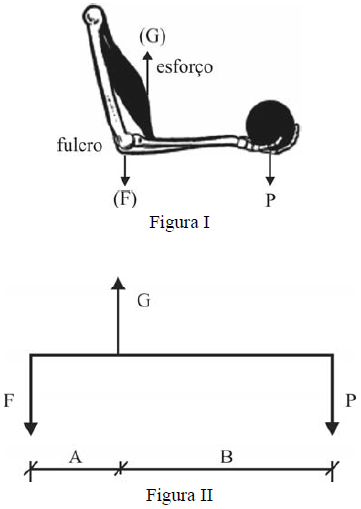

A figura I, abaixo, ilustra o braço humano, cujo movimento é similar ao de uma alavanca com ponto de apoio no fulcro. Na figura I, o braço está segurando um objeto de peso igual a P, enquanto o músculo em destaque se contrai, criando um esforço contrário ao peso. Na figura II, é apresentado um diagrama de forças, que mostra uma situação de equilíbrio estático.

Considerando essas informações e as figuras I e II, verifica-se que